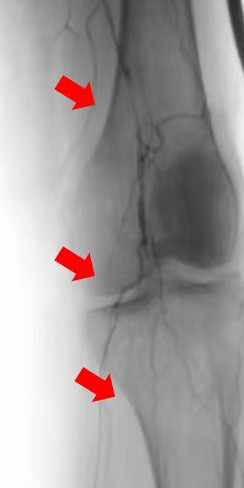

箭头所示:右腘动脉血栓栓塞,血流中断

术后右下肢动脉血流复通

箭头所示:左股、腘动脉血栓栓塞,血流中断

术后:左股腘动脉血流复通